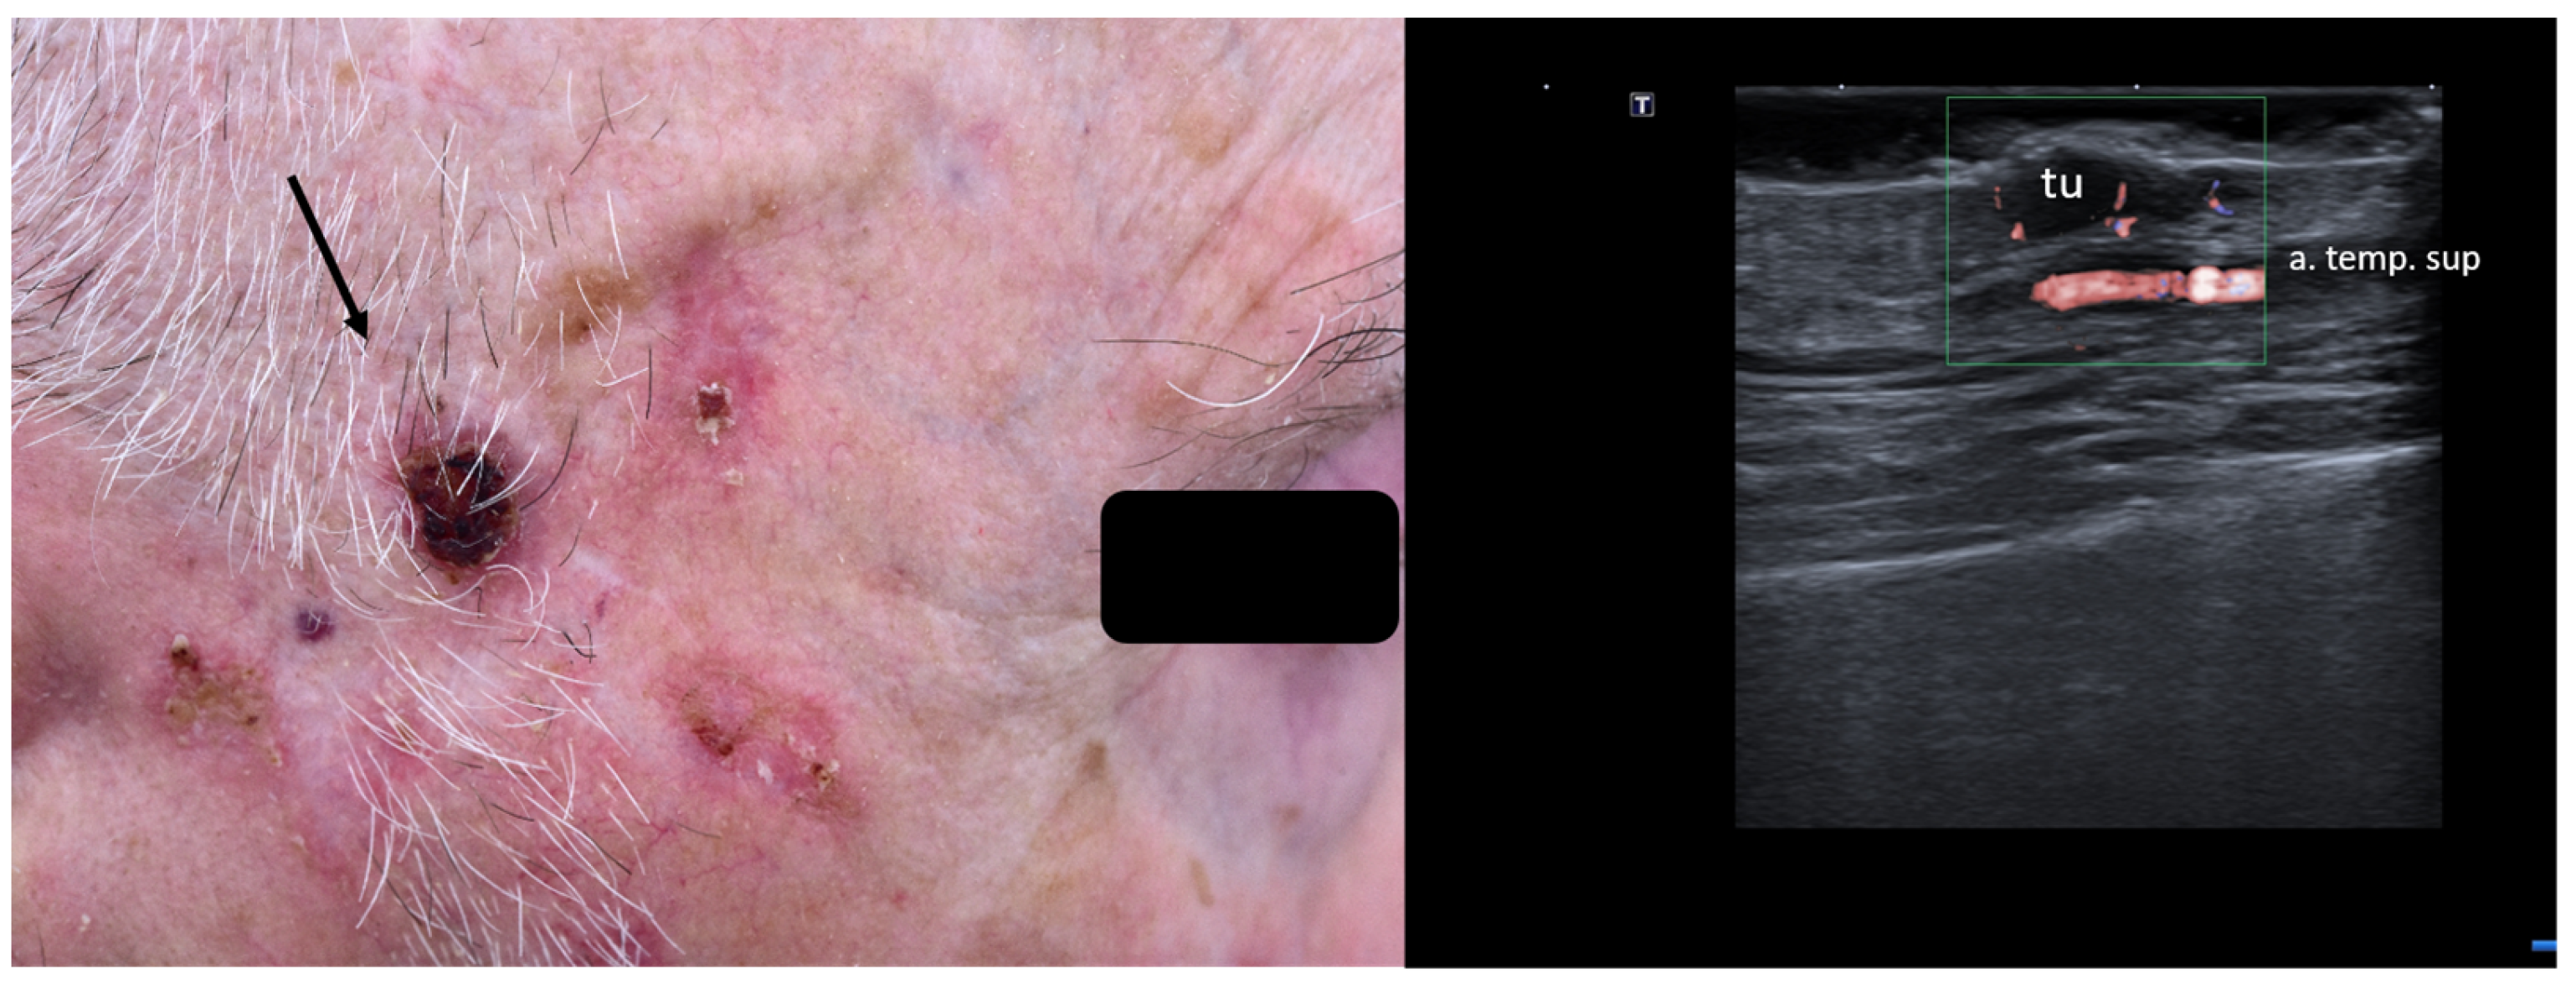

2. Enhancement of Diagnostic Accuracy, Avoidance of Misdiagnosis, Early Identification of Local Relapse

7. Choice of Surgical Approach

8. Preoperative Neuro-Vascular Mapping